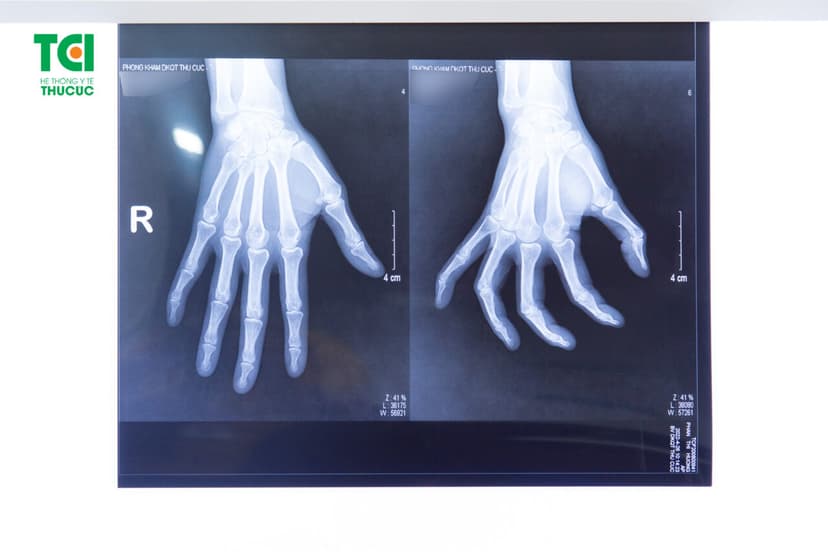

-Kiểm tra tình trạng biến dạng ngón tay: Ngón tay bị gãy di lệch nhiều sẽ biểu hiện rõ trên da. Bạn có thể so sánh giữa tay bị chấn thương và tay lành để nhận biết.

Gãy ngón tay không thể tự xử lý mà cần được thăm khám bởi bác sĩ để được điều trị đúng cách, tránh biến chứng. Đáp ứng nhu cầu khám chữa bệnh của nhiều người, Bệnh viện Đa khoa Quốc tế Thu Cúc đã trang bị cho mình hệ thống máy móc hiện đại như máy chụp X quang, máy chụp CT,… cùng đội ngũ bác sĩ có trình độ chuyên môn cao, giàu kinh nghiệm giúp đưa ra các đánh giá chính xác và phương pháp điều trị hiệu quả.